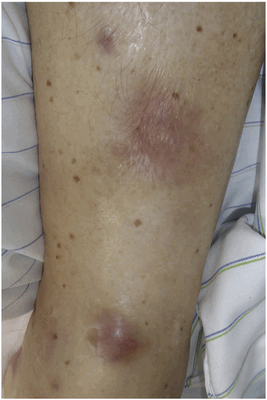

Со стороны кожи наблюдаются гелиотропная сыпь (красные или лиловые высыпания на веках, иногда - на лице, шее и туловище) и симптом Готтрона (розовые или красные шелушащиеся бляшки и узелки по разгибательной поверхности мелких и средних суставов конечностей). Возможно также поражение легких, сердца, суставов, желудочно-кишечного тракта и нарушения со стороны эндокринной системы. Примерно у четверти пациентов возникают проявления только со стороны мышц. В этом случае болезнь носит название полимиозит.

Полиартрит в сочетании с панникулитом, напоминающим узловатую эритему, неоднократно описывался у пациентов с панкреатитом и высоким уровнем сывороточной липазы. Такие же проявления можно наблюдать и при ацинарно-клеточном раке поджелудочной железы, который также приводит к чрезвычайно высоким концентрациям липазы в кровотоке (Рис. 2). Это вызывает обширные некротические поражения подкожной жировой клетчатки с окружающей воспалительной реакцией. Полиартрит чаще всего поражает голеностопные, коленные, лучезапястные и пястно-фаланговые суставы. В более чем 130 публикациях ППП ассоциируется с неблагоприятным прогнозом.

Рисунок 2. Узелковое воспаление подкожной клетчатки у пациента с панкреатическим панникулитом и полиартритом и ацинарно-клеточным раком поджелудочной железы.